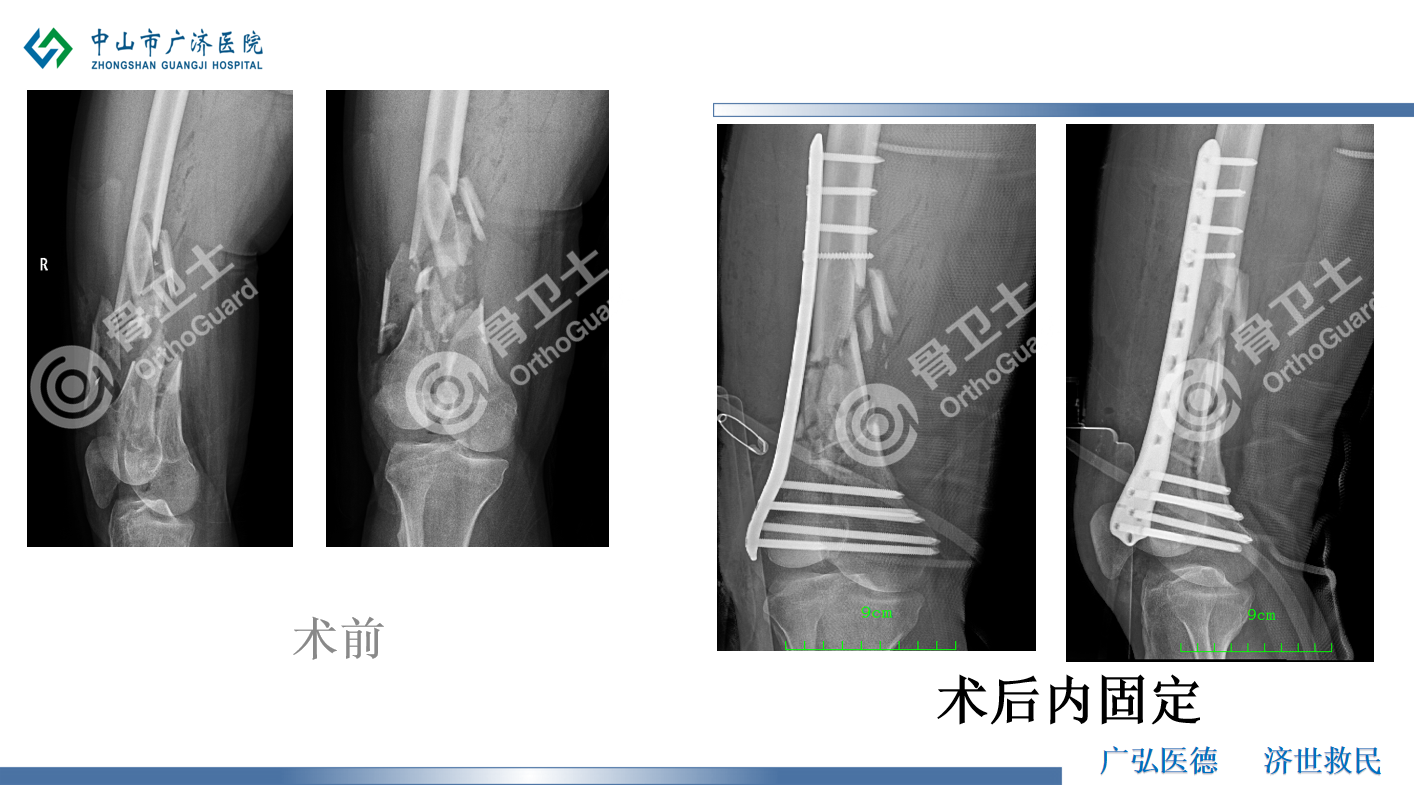

基本情况:男,38岁,因“摔伤致右大腿疼痛、出血伴活动受限1小时”入院。诊断:右股骨中远段粉碎性开放性骨折(Gustilo Ⅲ A型),右臂丛神经损伤,下颌皮肤挫裂伤,右侧第10后肋骨折,右肺轻度挫伤,左侧输尿管多发结石伴左侧肾盂及左侧输尿管上段轻度积水。治疗经过:伤口清创,复位股骨髁骨折端并行克氏针临时固定股骨髁骨折,右股骨远端外侧钢板置入,自体骨植骨,石膏托外固定。

杨述华教授表示,该病例的处理非常恰当,基本达到解剖复位的标准。股骨下端开放性粉碎性骨折处理起来是非常棘手的,开放性骨折的处理中,彻底清创是预防感染的重要手段,及时清除没有活力的组织,污染的骨块要及时、彻底消毒,碎骨块不要丢弃。对于伤口较大的粉碎性骨折,建议不要在一期手术时放入较大内固定,可以选择钢丝、克氏针等方式予以临时固定,同时搭配外固定或骨外牵引是比较稳妥的方式。中山市广济医院选择的钢板置入+自体骨植骨的方式也是值得鼓励的。对于患者上肢三角肌外展功能受限,肱二头肌、前臂斜后肌功能未恢复的情况,杨述华教授认为,患者手指运动正常,但外展功能受限,臂丛神经损伤不能完全排除,建议做臂丛神经和颈神经成像检查,确定神经损伤情况。由于患者颈3-4、颈4-5、颈5-6、颈6-7都有椎间盘突出,颈椎引起的颈脊髓损伤也不能排除。此外,还需要考虑脊髓休克征,颈脊髓受到创伤后,可能发生暂时性、一过性发生功能障碍,表现出瘫痪的症状,但磁共振检查神经并没有损伤,只是暂时的功能障碍,这类患者早期可以不做手术,观察8-12个小时,如慢慢恢复功能,则说明没有手术指征,可以慢慢恢复。但杨述华教授主张积极处理神经损伤问题,而不是保守观察。